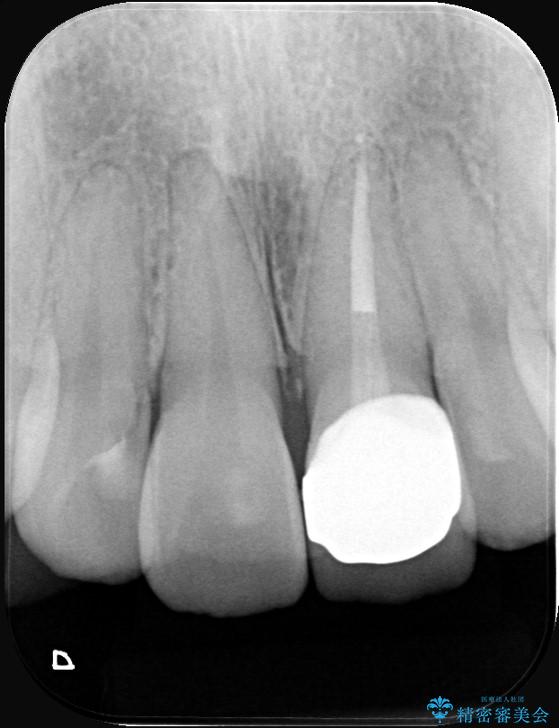

- 「以前、他院で神経を取った前歯がだんだん黒ずんできた」という見た目の改善を主訴にご来院されました。 診査の結果、神経を取り除いた後の歯(失活歯)特有の変色が起きており、さらに根の先端にわずかな影が見られたため、内部で感染が起きている可能性がありました。

そこで、まずは土台を外して根の内部をきれいにする再根管治療を行い、基礎をやり直した上で、透明感の高いオールセラミッククラウンで被せ直す治療計画を立案。単に白くするだけでなく、再発を防ぎ、長期的に美しい状態を保つことを目指しました。

精密な再根管治療: 古い充填材を除去し、歯科用顕微鏡を用いて根管内を徹底的に清掃・殺菌しました。根の先まで確実に薬剤を詰め直すことで、将来的な根尖病変(根の先の膿)のリスクを最小限に抑えました。